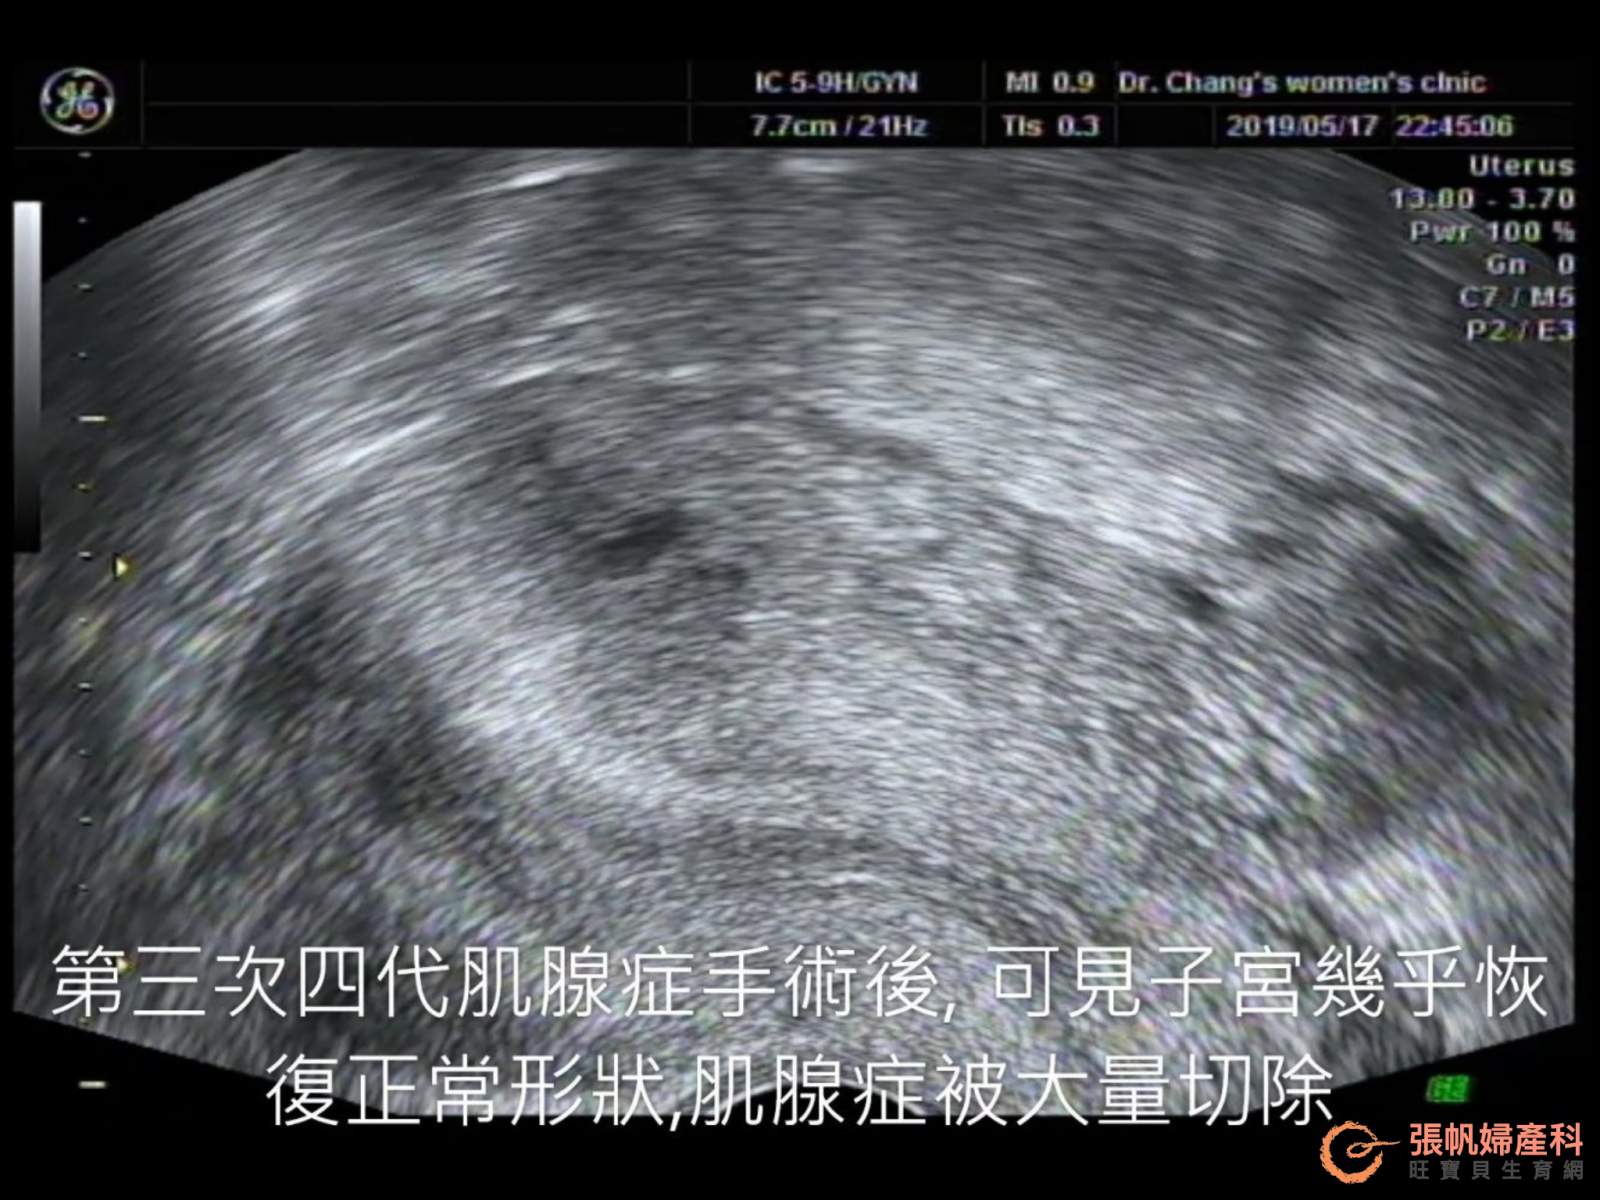

► 中藥調理後肌腺症再次復發 第三次第四代肌腺症手術後被大量清除

在今年年初,吃了六個月中藥調理後的她,帶著蒼白的臉色回來診所,這時的超音波檢查,發現肌腺症又復發了,所以經血變多了,看著紀錄上她當時經dhea調整後培養上來的兩個囊胚,我又很不情願的建議她再次手術...

在這一年多的時間裡,我的手術方式又悄悄地進步了一代,這是在歐洲開醫學會,看到歐洲人開刀後的啟發,回來後改變了手術方式,利用超音波導引,可以看穿子宮,了解肌腺症的確實位置,而不是光用手摸來判斷... 初期的幾個病人,恢復得都很好,看著她已有很好的胚胎,攻頂之路,卡在不完美的子宮,雖然再次手術風險大,不是醫生的選項,但為了病人,這個險還是得冒!

► 第一位重複手術病人順利完成 休息後CA-125完全正常 植入後成功達成雙胞胎

和病人討論取得共識後,我們再次開了剖腹手術,這是診所開的一百多例肌腺症手術的第一位重複手術的病人,手術順利完成,開完後子宮看來,好像完全沒有肌腺症了!(自己臭美!)休息了三個月後,我們測了下ca-125,居然完全正常,所以這次的冷凍胚胎植入,完全沒打停經針,解凍了兩個囊胚植入,順利達成了一對雙胞胎!